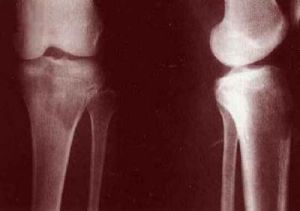

3、骨骼臨床表現有局部骨骼疼痛及繼發性神經壓迫症狀;

2)x線檢查,下肢的淋巴管造影,對確定腹膜後淋巴結受侵有一定價值。對其他可疑的部位作x線攝片和造影檢查亦很有診斷價值。